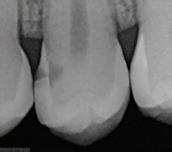

In the endodontic stage, conservative endodontic preparation and obturation with modern techniques are performed as they are for any tooth. All endodontic procedures are performed under an operating microscope to maximize visualization and illumination of the fracture line (Fig 1). The coronal portion of the newly placed gutta percha is removed 2 to 3 mm below the deepest extent of the crack in the affected canal to prepare for intraradicular barrier placement (Fig 2). Gutta percha is also removed 2 to 3 mm into the other noncracked canal orifices in the tooth to prepare for traditional orifice barriers. Microscopic transillumination with a fiber-optic light, in which an LED light probe is placed against buccal or lingual tissues overlying the roots, is utilized to illuminate the root and enhance visualization of the crack (Fig 3). A flowable resin-modified glassionomer or composite resin is then placed in this newly created void from the level of the gutta percha to the floor of the pulp chamber in all canal orifices (Fig 4). A composite resin core is then placed to permanently restore the endodontic access. If a temporary or permanent crown is not placed immediately after the endodontic procedures, the tooth is reduced

Periapical radiograph at the completion of the endodontic protocol. Resin-modified glass ionomer cement is placed as an intraradicular barrier in the distal canal, along the pulpal floor, and as an orifice barrier in the mesial canals.

The placement of intraradicular barriers in the described protocol is based on empirical data supporting their efficacy in improving both the seal and fracture resistance at the pericervical dentin. Studies on canal orifice barriers have noted that a minimum of 2 to 3 mm of material is necessary to create a coronal seal.28,29 In this protocol, removal of gutta percha to this depth was chosen to maximize the seal below the level of the crack on intact dentin. Studies have also shown that placement of these barriers can enhance the pericervical dentin’s

Fig 1. Microscopic visualization of the radicular extension of the crack (arrows) entering the canal.

Fig 2. Gutta percha removed 2 mm apical to the terminus of the fracture (arrows).